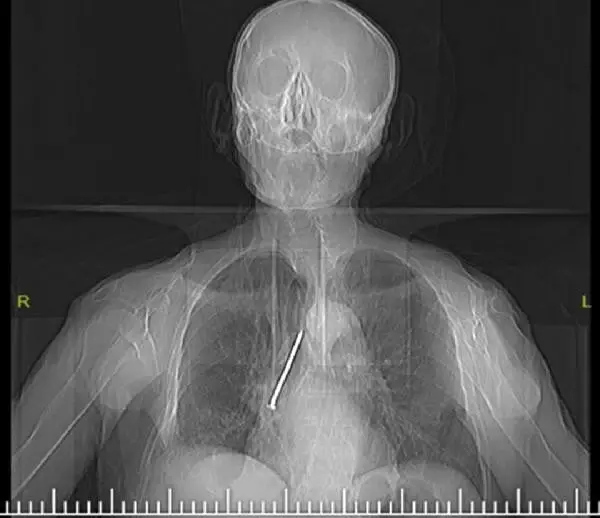

ELAZIĞ’da öksürük ve nefes darlığı şikayetiyle hastaneye başvuran Keko Ateş’in (91) nefes borusunda 10 santimlik çivi tespit edildi. Ateş’in, 24 yıl evvel Larenks kanseri ameliyatı sırasında nefes borusunda açılan açıklığı temizlemek için kullandığı çivinin soluk borusuna kaçtığı belirlendi.

Keko Ateş, öksürük ve nefes darlığı şikayetiyle Fethi Sekin Kent Hastanesi’ne başvurdu. Yapılan tetkik ve muayenelerden sonra Ateş’in nefes borusunda çivi olduğu tespit edildi. Hastanın hayatını tehlikeye atan bu durumun giderilmesi için Ateş, Göğüs Cerrahi Uzmanı Dr. Öğr. Üyesi Murat Kılıç tarafından operasyona alındı. Soluk borusun içerisinde ve sağ akciğer içerisine gerçek kaçmış olan 10 santim uzunluğundaki çivi, ‘Rijit Bronskoskopi’ süreciyle çıkarıldı.

Dr. Öğr. Üyesi Murat Kılıç, Larenks kanseri olan Ateş’in, 24 yıl evvel Total Larenjektomi ameliyatı sırasında boynundan nefes borusuna açılan açıklığı temizlemek için kullandığı çivinin soluk borusuna kaçtığını anlattı. Dr. Öğr. Üyesi Kılıç, “Bu nedenle gelişen öksürük ve nefes darlığı şikayeti ile evvel öbür bir sıhhat merkezine başvuran, akabinde Fethi Sekin Kent Hastanemiz Göğüs Cerrahisi Kliniği’ne yönlendirilen hastaya çektiğimiz tomografide soluk borusu içerisinde ve sağ akciğer içerisine yanlışsız kaçmış olan bir çivi olduğunu tespit ettik. Bunun üzerine hastamızı acil olarak ameliyata aldık. Uyguladığımız Rijit Bronskoskopi süreci ile nefes borusundaki 10 santimlik çiviyi başarılı bir halde çıkardık. Hastamızı ameliyat sonrası bir mühlet serviste takip ettikten sonra gün içerisinde şifa ile taburcu ettik” dedi.